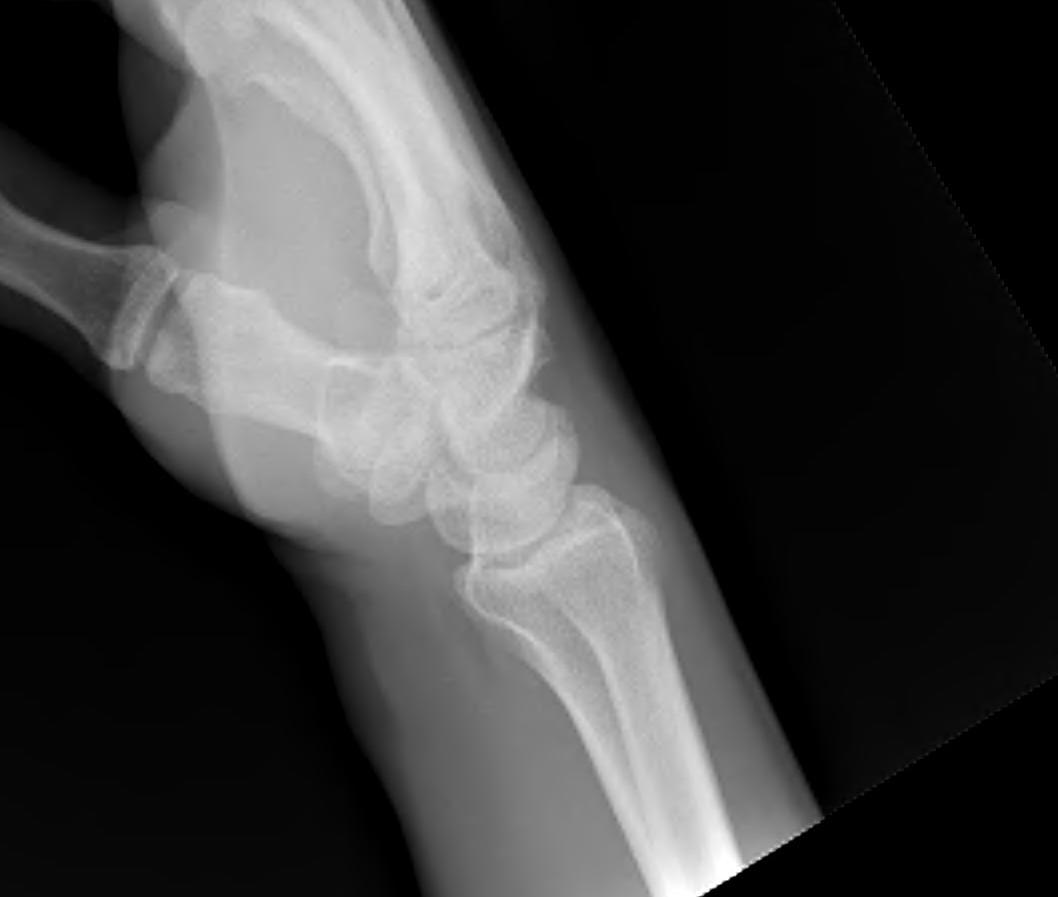

Lateral

Palmarflexion of scaphoid

Dorsiflexion of lunate

Increased scapholunate angle

- > 70o

- usually 30 - 60o

Increased luno-capitate angle

- normally < 10o

Increased radio-lunate angle

- lunate extended > 10o